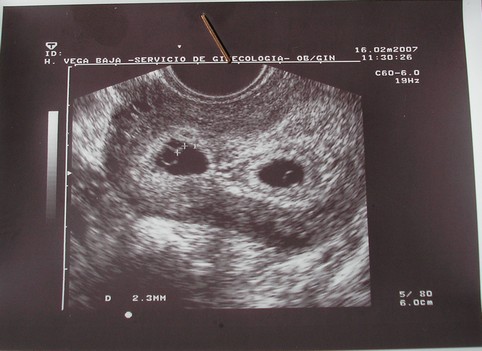

Sütőtök - És gratuláltunk már???? ha még nem:

GRATULÁLOK!!!!!!!!!!!!!!